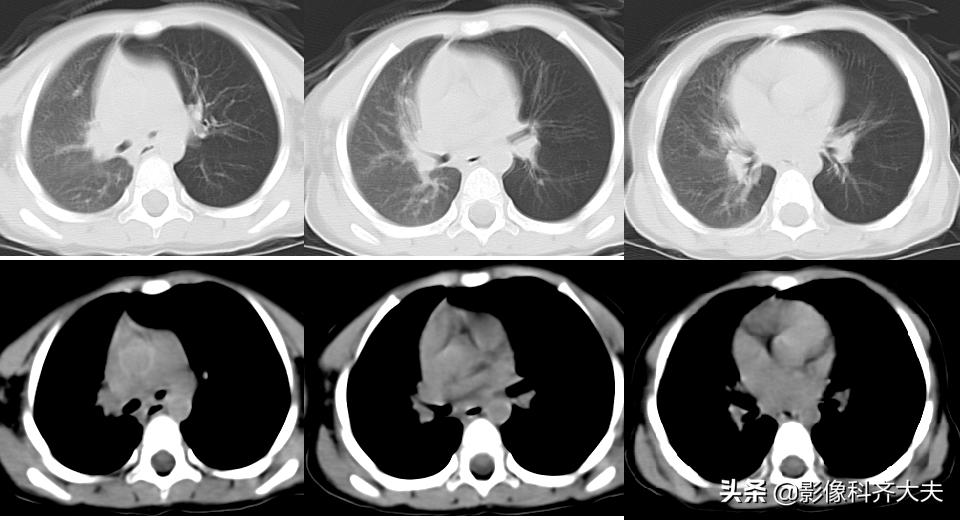

病例2、病史:患儿,男、1岁9个月,咳喘20天。家属否认异物吸入史。

图为正位普通X线片,显示左侧明显肺气肿改变,提示左侧支气管异物可能,因家属否认异物吸入,遂进一步做CT确诊。

CT冠状位重建明确显示左侧自气管阻塞,有明确异物的存在,红色箭头所示。